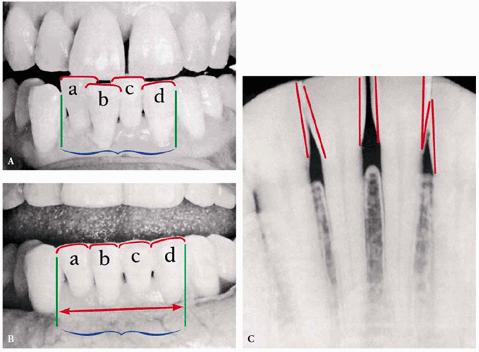

This formula can aid in the correction of crowded or spaced teeth by measuring

the amount to be added or subtracted for the desired objective (Figures 24-1A to

C

Figure 24-1A to C: (A) Preoperative view: note the relationship of the combined widths of the lower central and lateral teeth (A, B, C, D) to the extent of available arch space. Sum of combined tooth widths > available arch space, resulting in buckling. (B) Postoperative measurement, after remodeling of the lower central and lateral incisor teeth: the combined tooth widths equal the available arch space, and repositioning of the teeth became a feasible clinical procedure. (C) The proximal thickness of the enamel "caps" of the teeth on a lower anterior segment of the dental arch is indicated in outline. (Reproduced with permission from Berliner A. Ligatures, splints, bite pla 737j923h nes and pyramids. Philadelphia: JB Lippincott, 1964:65.)

If the evaluation of arch space, as previously described by Berliner,2

shows that the combined addition of ABCD in the lower arch equals 21 mm (see Figure 24-1A) but the available space is 20 mm,

the amount of crowding is 1 mm. Therefore, if minor movement or repositioning

is attempted to realign the teeth, 1 mm of combined mesiodistal width can be

sacrificed through discing. However, not all of the tooth surface will have to

be lost from the central and lateral incisors. The mesial surfaces of the

cuspids are also available and, under certain rare conditions, the distal

surfaces of cuspids as well.

One

limitation on reducing tooth structure through discing is the thickness of

enamel on the teeth. Radiographs must be accurate enough to measure the

available enamel. A measurement can be made of the proximal surfaces on each of

the anterior teeth to predict the maximum reduction possible without

perforating the dentin.

For example, if 0.25 mm is found to be the amount that can be reduced per

proximal surface, then 0.5 mm can be reduced per tooth. Therefore, 3.0 mm could

theoretically be reduced from the six anterior teeth by discing to increase the

available arch space. In applying this to the earlier example of 1-mm crowding,

there should be no repositioning problem.

The procedure for applying the above principle is as follows:

1. Measure the mesiodistal width of the individual teeth and the available arch

space with a dental dial caliper.

2. Measure the enamel thickness by studying the radiographs of the involved

anterior teeth (see Figure 24-1C). Peck and Peck caution that

accessing enamel thickness from radiographs alone is subject to possible

distortion.32 Instead, they offer an arbitrary, but safe, guideline

of 50% of the mesiodistal enamel thickness as the maximum limit of

reproximation.